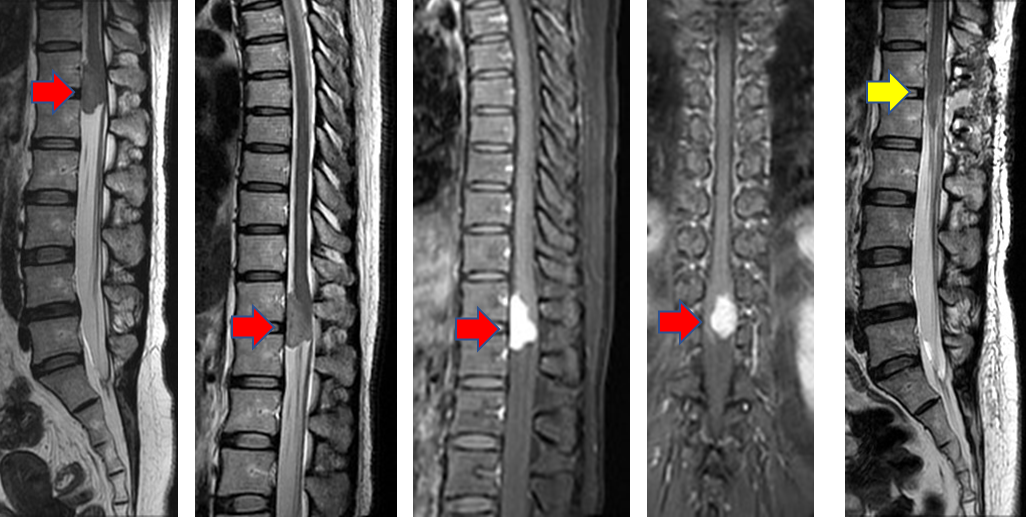

肿瘤长约3cm

术前(红箭头)和术后(黄箭头)对比影像